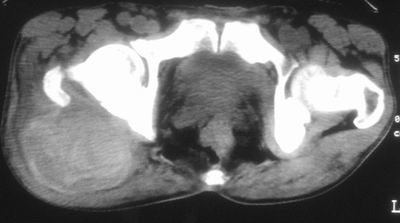

标题: CT16837:M63Y,右臀部巨大软组织包块 [打印本页]

标题: CT16837:M63Y,右臀部巨大软组织包块

患者,男,63岁,自诉3个月前发现右臀部包块,触及疼痛,治疗后缩小。前天突然增大。无高热病史。

考虑-----右臀大肌,臀中肌---感染性病变可能性大。

恶性软组织肿瘤可能性不大

病灶内部可见出血,首先考虑急性出血性病变.血肿?

给个骨窗,判断一下肿块是否与髂骨有关,肿块内出血是肯定的,至于是感染形成的脓肿还是起源于肌肉或纤维组织的肉瘤则难以确定,不过从影像上看,包膜完整,且环形增厚,病灶下部见斑片状底密度坏死,个人倾向感染可能性大

肌间隙明显混浊,三个月前治疗有缩小,支持考虑臀大肌下脓肿伴出血,肿瘤如果出现瘤内出血的话瘤外边界应该较清楚,现在表现为一种恶性征像,但骨质无明显异常,且臀小肌边界清楚,不符合恶性表现.